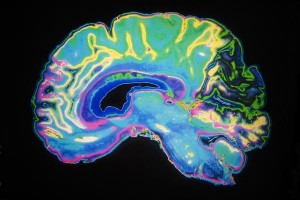

Magnus: La muerte cerebral es la pérdida total y permanente de todas las principales funciones integradoras del cerebro, incluyendo la corteza cerebral y el tronco cerebral. Con el desarrollo de la ventilación mecánica, la vieja comprensión del significado de la muerte como el cese irreversible de la función circulatoria y respiratoria llegó a ser cuestionada. En 1968, un comité ad hoc de Harvard recomienda que los pacientes que han perdido la función cerebral deben considerarse muertos. En 1981, la Comisión Presidencial para el Estudio de Problemas Éticos en Medicina y la Investigación Biomédica y Conductual proporciona una definición que ayudó a explicar por qué la muerte cerebral es la muerte – la pérdida de las funciones clave que integran la persona y su cuerpo. Los neurólogos tienen normas muy claras que les permitan determinar con mucha precisión cuando alguien cumple con los criterios neurológicos de la muerte y, si se siguen correctamente, no hay prácticamente ningún falso positivo. Como resultado, la muerte cerebral ha sido reconocida en cada estado durante décadas.